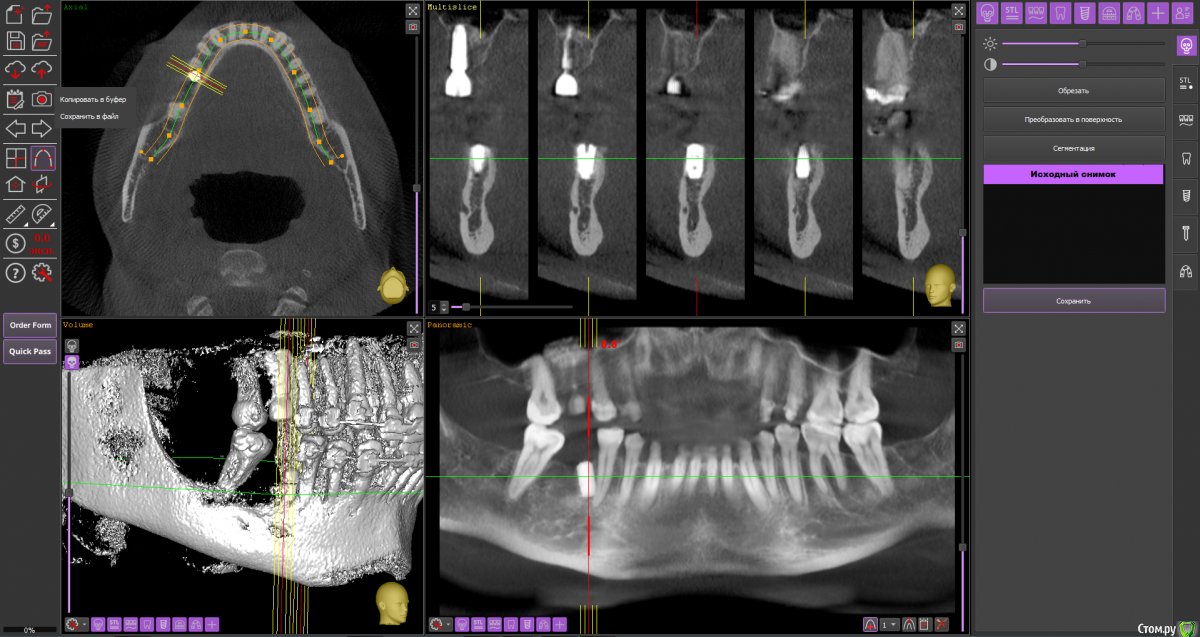

Тата Богачевская Опубликовано 24 октября, 2020 Поделиться Опубликовано 24 октября, 2020 Здравствуйте. Меньше месяца назад на место отсутствующего 46 зуба мне был установлен имплантат с расщеплением альвеолярного гребня. Операция прошла хорошо, никаких осложнений. В настоящий момент ничего не беспокоит. Тем не менее положение имплантата у меня вызывает беспокойство - слишком близко к корню 45 зуба и под углом к нему. Однако доктор уверяет, что положение имплантата нормальное, не идеальное конечно, но не критичное. Скажите, пожалуйста, угрожает ли такое положение имплантата 45 зубу, возможно ли будет в дальнейшем установить коронку в правильное положение? Или нужно удалить имплантат? Благодарю.https://yadi.sk/d/Tzd1aKb84eU3wQ Ссылка на комментарий

Тата Богачевская Опубликовано 25 октября, 2020 Автор Поделиться Опубликовано 25 октября, 2020 1.png2.png3.pngВы сделали то, что попросил red butler? Это и есть срезы? Большое спасибо. Ссылка на комментарий

red_butler Опубликовано 25 октября, 2020 Поделиться Опубликовано 25 октября, 2020 Имплант нужно переставить Ссылка на комментарий

колесников Опубликовано 25 октября, 2020 Поделиться Опубликовано 25 октября, 2020 4 месяцаИмплант 46 нужно убрать. Зуб 47ой дистализировать ортодонтически. Переустановить имплант 46 в правильной ортопедической позиции с десневой пластикой. К окончанию лечения вероятно будут вопросы к импланту 16,положение его платформы не самое оптимальное . 1 Ссылка на комментарий